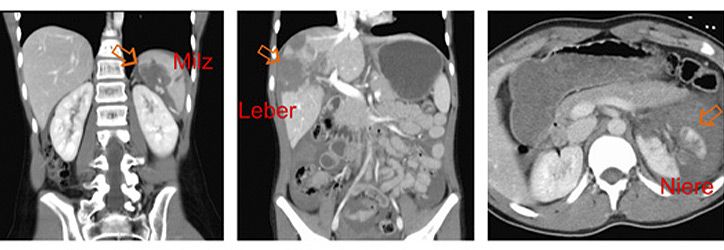

Verletzungen der Bauchorgane

Die Bauchorgane werden in Europa fast ausschließlich durch stumpfe Traumen verletzt. Die Unfallursachen sind altersabhängig und bei Kleinkindern v.a. Stürze, bei Schulkindern zunehmend Sportunfälle und in allen Altersgruppen Verkehrunfälle. Am häufigsten sind Milz, Leber und Nieren (Abbildung) verletzt, seltener die Bauchspeicheldrüse oder der Magen-Darm-Trakt.

Bei Kindern gibt es die Besonderheiten einer noch schwach ausgebildeden Muskulatur des Bauches und flüssigkeitsreichere Organe, die relativ gesehen größer sind als bei Erwachsenen. Führendes Leitsymptom beim Bauchtrauma ist der Bauchschmerz, es können aber auch Übelkeit und Erbechen vorliegen. Wichtig ist zu unterscheiden zwischen isoliertem Bauchtrauma und Patienten mit Mehrfachverletzungen/Polytrauma.